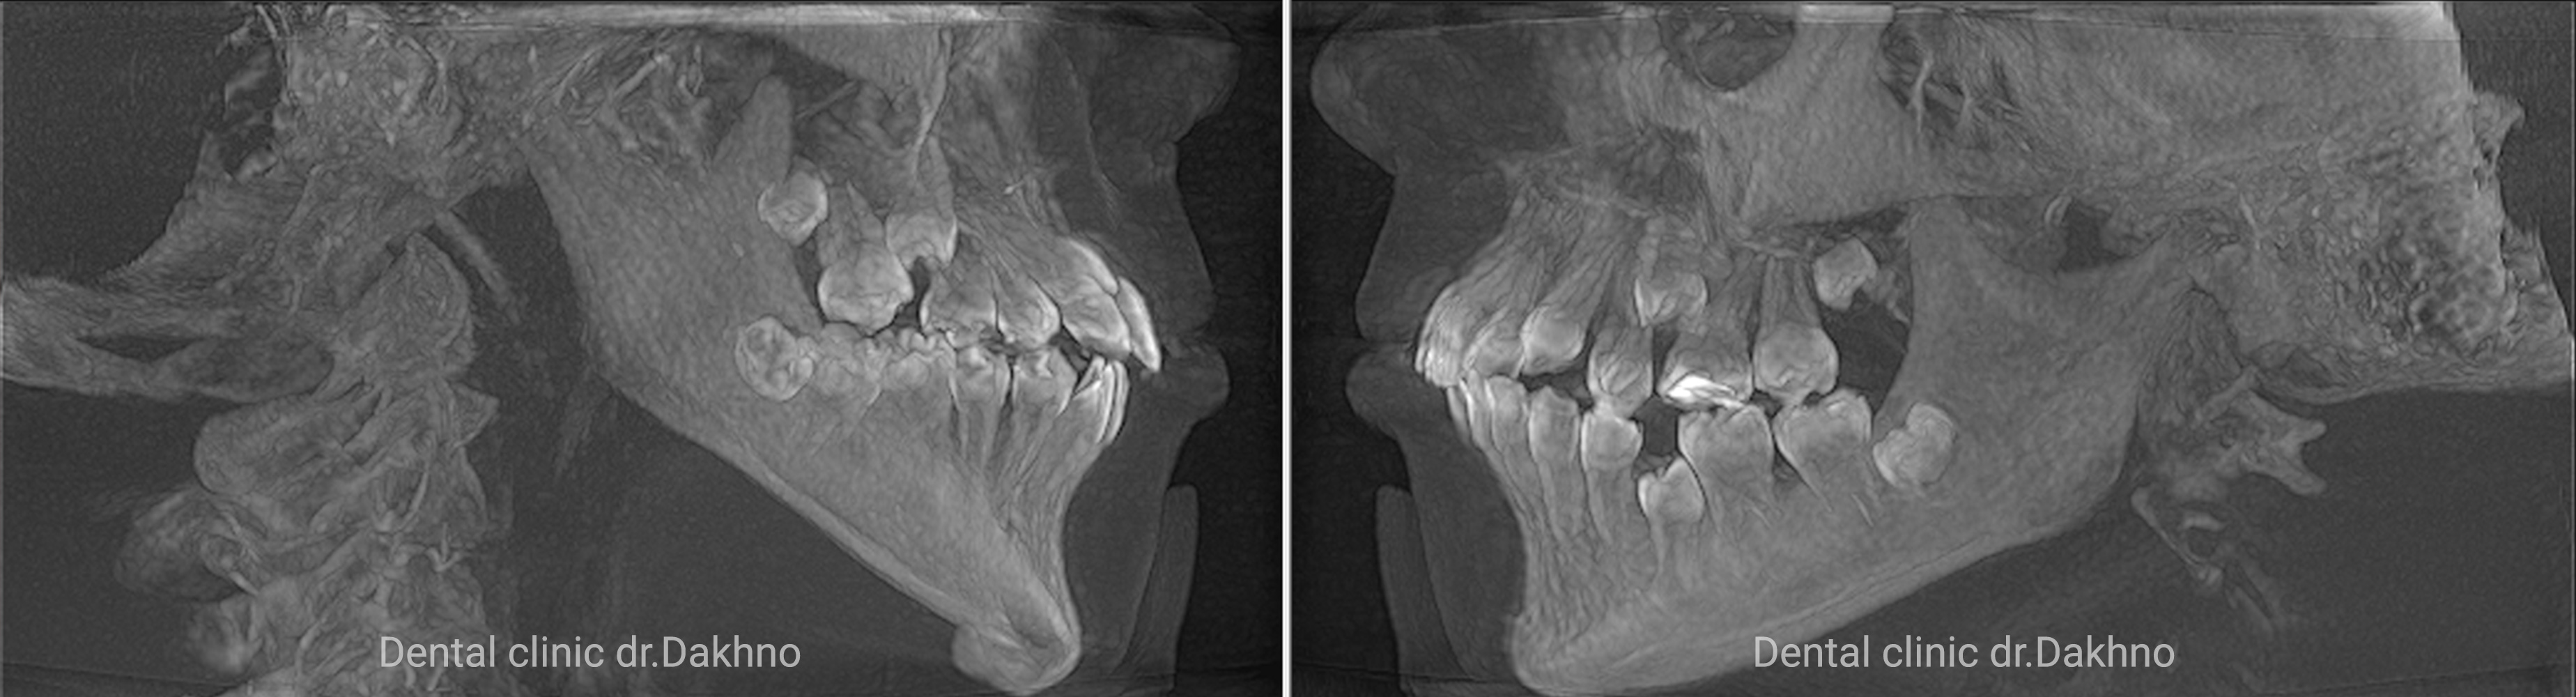

Клінічний діагноз: вертикальний тип росту і розвитку нижньої третини обличчя, бімаксілярна мікрогнатія, звуження і деформація зубних рядів верхньої і нижньої щелепи, скученість зубів.

Липень 2017 Батьки звернулися в клініку з метою виправлення скученості зубів. Після отримання необхідних діагностичних даних: виконання КПКТ (конусно-променевої комп’ютерної томографії), фотопротокола і отримання діагностичних моделей прийнято рішення першим етапом ортодонтичного лікування виконати розширення верхньої щелепи за рахунок фіксованого апарату HYREX на оклюзійних накладках.